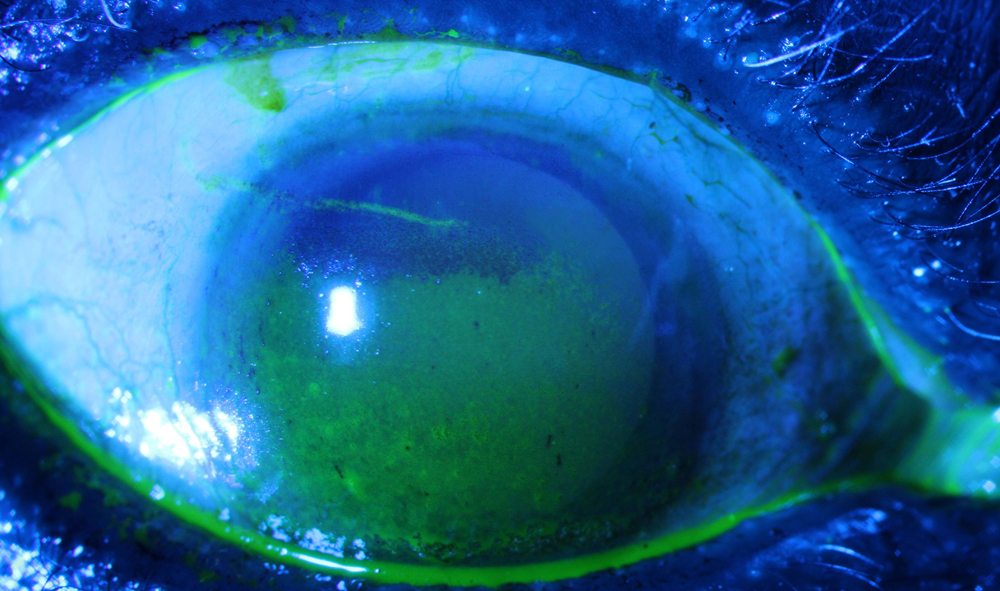

Source: Vatinee Y. Bunya, MD, MSCE

- Abnormal ocular staining score of ≥5 (or a van Bijsterveld score ≥4) (1 point)

She said individuals who meet eligibility criteria for Sjögren’s have a score of 4 or more. “Of note, the two ocular tests that are included in the criteria include an abnormal ocular staining score or an abnormal Schirmer test without anesthesia,” she said. “Therefore, it’s important for ophthalmologists to perform these two tests in any dry eye patient who may have Sjögren’s disease.”

Dr. Bunya also said that while there are newer diagnostic tests for dry eye disease, none have been shown to distinguish dry eye that is associated with Sjögren’s. “Ophthalmologists and optometrists play a critical role in diagnosing Sjögren’s patients early on in their disease, as many studies have shown that dry eye is one of the most common symptoms of Sjögren’s disease,” Dr. Bunya said. “I recommend that the ocular staining score and Schirmer test without anesthesia be performed on all new dry eye patients. Dry eye patients should be referred for systemic workups for Sjögren’s disease if they meet any of the ocular criteria, if they have a positive review of systems for symptoms such as joint pain, dry mouth, or fatigue, or if they have dry eye disease that is refractory to treatment.”

Source: Vatinee Y. Bunya, MD